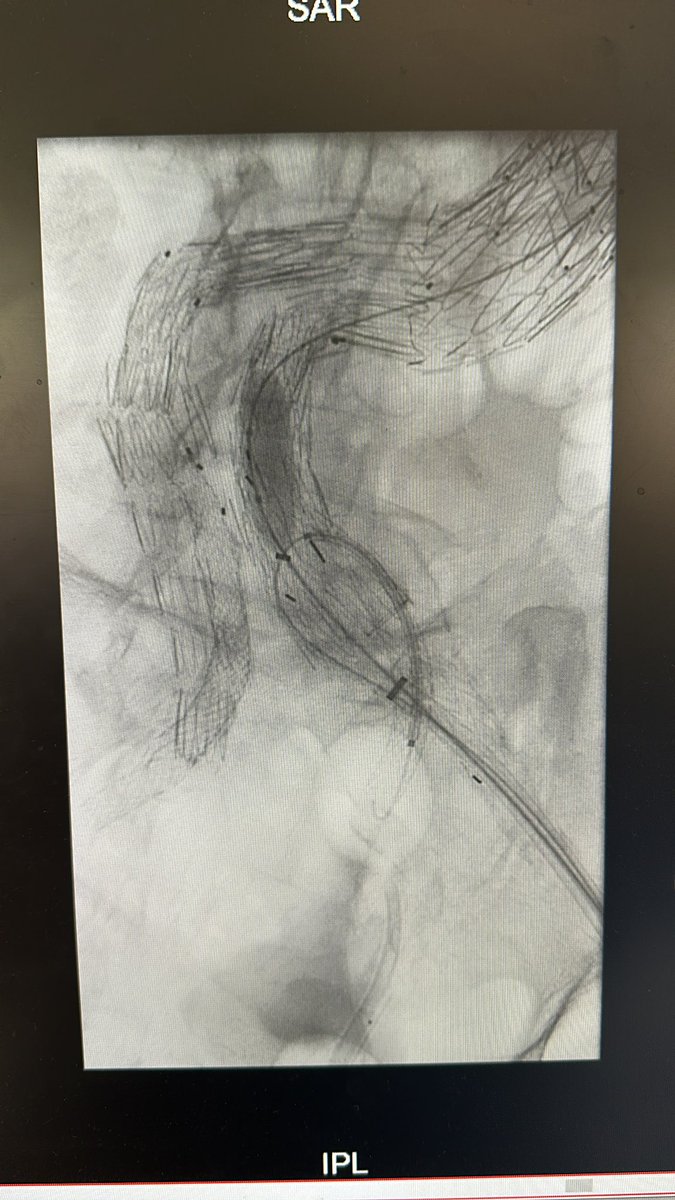

#OriginalResearch A multicenter study on the outcomes of physician-modified endografts in the treatment of aortic aneurysms @NTsilimparis ahajournals.org/doi/abs/10.116…